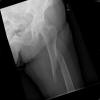

Fractura de cuello de fémur.

Fractura de cuello de fémur